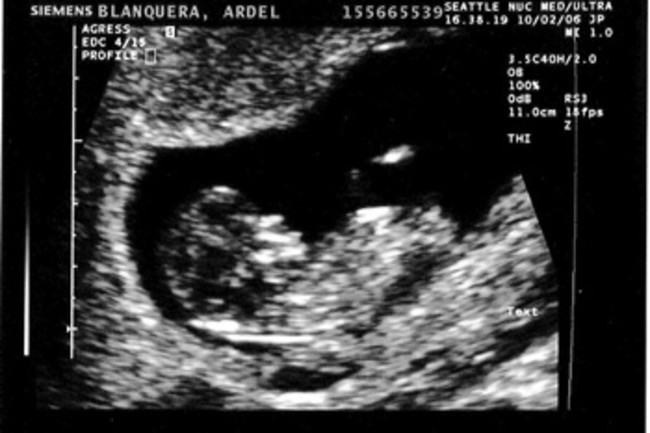

Ultrasounds may reveal sex organs by 14 weeks but they aren t considered fully accurate until 18 weeks.

In the conventional process you have to be on your fourth or fifth month of pregnancy to determine the baby s gender. Nipt is a blood test that s available to all pregnant women beginning at 10 weeks of pregnancy. You can also find out the sex of your baby by having noninvasive prenatal testing nipt a blood test which is usually done between 11 and 14 weeks of pregnancy. At 20 weeks the test got it right 99 of the time.

It screens for down syndrome and a few other chromosomal conditions and it can tell you whether you re having a boy or a girl. By holly lebowitz rossi. If you have a prenatal blood test nipt you may be able to find out your baby s sex as early as 11 weeks of pregnancy. Nipt results must be confirmed by a diagnostic test such as cvs or amniocentesis.

You probably won t find out your baby s sex until a few months into your pregnancy but it was set in stone at the moment of conception. But as early as seven weeks you can know your baby s gender through blood testing.